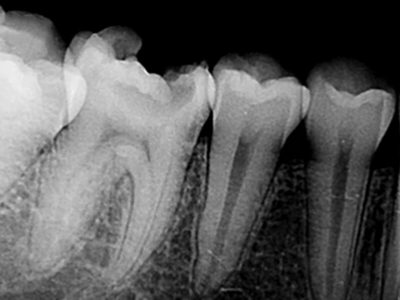

年轻恒牙龋指的是儿童萌出不久的第一恒磨牙龋病和上颌恒切牙龋病,其中第一恒磨牙龋病占年轻恒牙龋的90%,发病早,进展快,可表现为白垩色斑片、点隙窝沟墨浸状龋坏或龋洞。本病的发生和年轻恒牙的特点以及儿童饮食、口腔卫生等因素有关。

年轻恒牙龋好发于第一、二恒磨牙(牙合)面、邻面,上颌中切牙邻面,多为急性龋,龋坏进展快。平滑面的早期龋多为白垩色的斑片,点隙窝沟的早期龋多为浸墨状,表面粗糙。如果早期龋不及时治疗,可逐渐形成大而深的龋洞,易导致牙髓炎和根尖周炎。

年轻恒牙龋一般可进行充填治疗,对于早期的年轻恒磨牙,提倡采用微创的预防性树脂充填术、改良的预防性树脂充填术;深龋必要时考虑二次去腐修复。日常注意饮食,重视口腔卫生,考虑局部使用氟化物防龋,如含氟牙膏、含氟漱口水等,进行预防。对于年轻恒磨牙,可早期进行窝沟封闭,定期进行口腔检查。